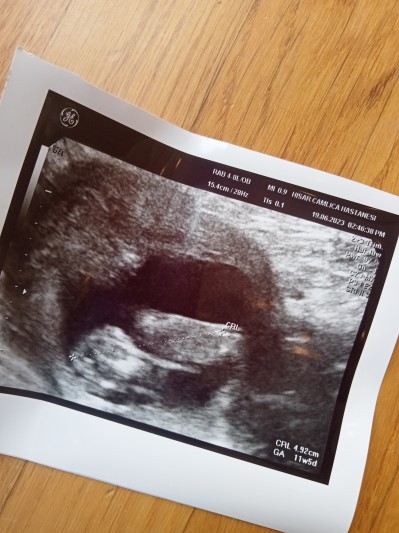

Bebek boyu 11+5 de 4.92 cm fakat  uygulamada haftasında 6 ile 14 cm arası olur  yazıyor normal mi bebeğimin boyu  kafama takıldı ilk gebelik bide daha önce bu haftalara gelemeden kaybetmiştim .

Gebelik haftası 11+5